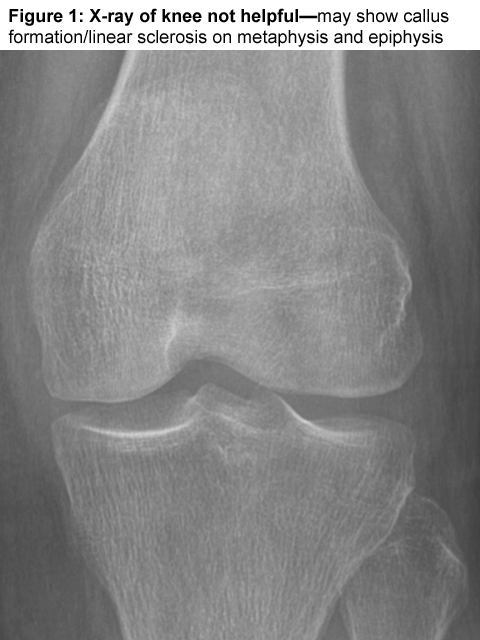

Abstract: Insufficiency Fractures (I.F) are non-traumatic fractures that occur in abnormal bone (low density bone). Usually occurs in elderly post-menopausal women and is non-traumatic. X-rays are unremarkable and MRI showed extensive bone marrow oedema and subchondral fracture.

MRI is the gold standard for Dx. I.F.

Symptoms and conventional tests may not be helpful, High Index of suspicious is needed.